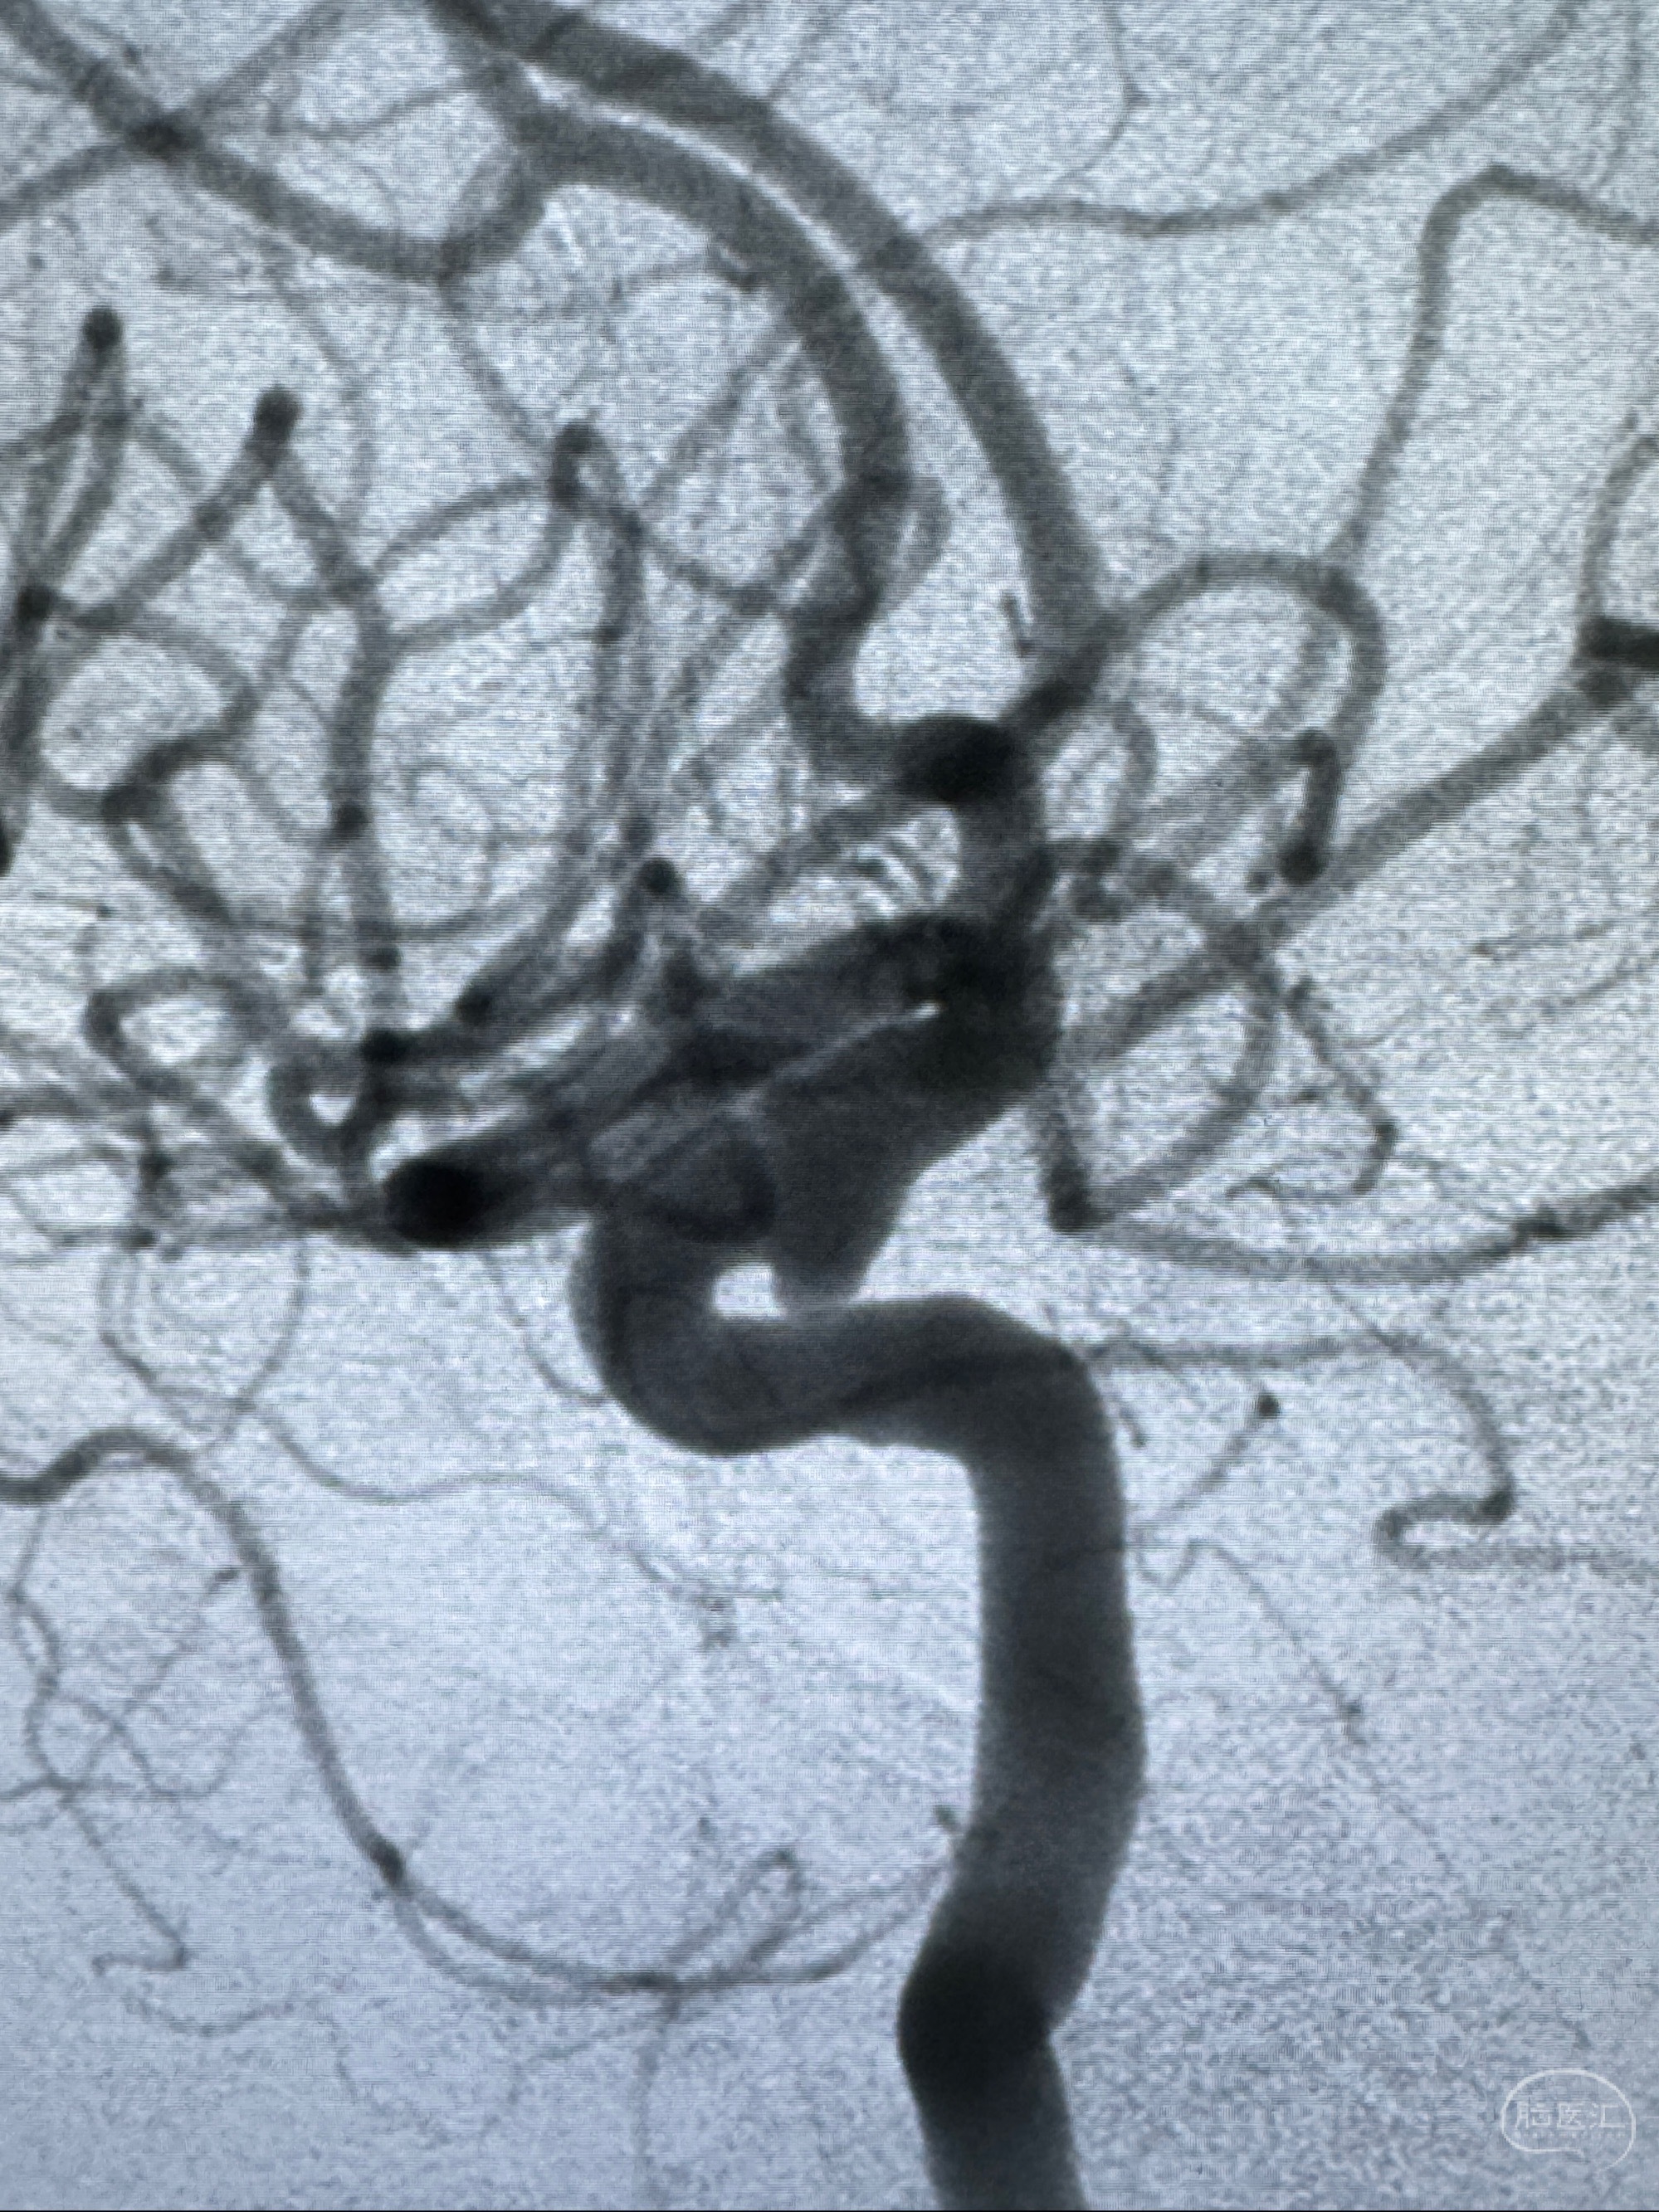

2023-11-29全麻下行NeuroformEZ4.5-20mm支架辅助栓塞

麻醉苏醒佳,遵嘱动作

术后即刻CT